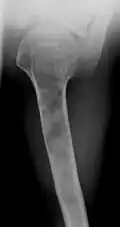

X-ray image showing enchondromas localized in the lower part of the radius of a 7-year-old girl with Ollier disease.

Abnormal bone growth such as shortening or thickening and deformity may be observed in patients of Ollier disease. These bone lesions are visible at birth using radiography but are usually not screened or examined for until clinical manifestations present during early childhood. However, some patients may exhibit no signs of any symptoms.[1] One study found thirteen to be the mean age of diagnosis in patients with Ollier disease. In an X-ray, there would normally be the presence of several homogeneous lesions of an oval or elongated shape with bone edges that are slightly thickened.[3] With age, these lesions may calcify and appear as diffusely minute spots or stippled. Fan-like septations or streaks would be indicative of the presence of several enchondromas. Early detection and consistent and repeated monitoring is important in order to prevent and treat any potential bone neoplasms.